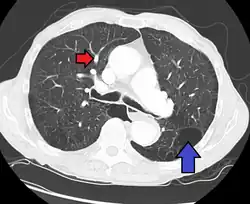

Pulmonary artery hypertension and emphysema as seen on a CT scan with contrast

Signs of pulmonary hypertension on CT scan of the chest are:

• Increased ratio of the diameter of the main pulmonary artery (pulmonary trunk) to the ascending aorta (measured at its bifurcation).

• A ratio of 1.0 is suggested as a cutoff in adults.[63]

• Cutoff ~1.09 in children.[63]

• Increased diameter ratio of segmental arteries to bronchi. This finding in three or four lobes, in the presence of a dilated pulmonary trunk (≥29 mm), and absence of significant structural lung disease confers a specificity of 100% for pulmonary hypertension.[63]

• Mural calcification in central pulmonary arteries is most frequently seen in patients with Eisenmenger's syndrome.[63]